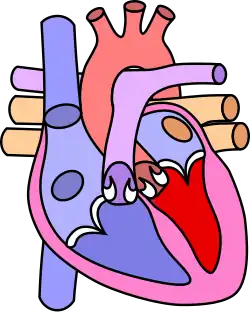

![]() | |

| Diagram of a healthy heart and one with tetralogy of Fallot | |

Four malformations

"Tetralogy" denotes four parts, here implying the syndrome's four anatomic defects.[2] This is not to be confused with the similarly named teratology, a field of medicine concerned with abnormal development and congenital malformations (including tetralogy of Fallot). Below are the four heart malformations that present together in tetralogy of Fallot:

| Pulmonary Infundibular Stenosis | A narrowing of the right ventricular outflow tract. It can occur at the pulmonary valve (valvular stenosis) or just below the pulmonary valve (infundibular stenosis).[4] Infundibular pulmonic stenosis is mostly caused by the overgrowth of the heart muscle wall (hypertrophy of the septoparietal trabeculae),[42] however, the events leading to the formation of the overriding aorta are also believed to be a cause. The pulmonic stenosis is the major cause of the malformations, with the other associated malformations acting as compensatory mechanisms to the pulmonic stenosis.[43] The degree of stenosis varies between individuals with TOF and is the primary determinant of symptoms and severity. This malformation is infrequently described as sub-pulmonary stenosis or subpulmonary obstruction.[44] |

| Overriding aorta | An aortic valve with biventricular connection, that is, it is situated above the ventricular septal defect and connected to both the right and the left ventricle. The degree to which the aorta is attached to the right ventricle is referred to as its degree of "override." The aortic root can be displaced toward the front (anteriorly) or directly above the septal defect, but it is always abnormally located to the right of the root of the pulmonary artery. The degree of override is extremely variable, with 5–95% of the valve being connected to the right ventricle.[42] |

| Ventricular septal defect (VSD) | A hole between the two bottom chambers (ventricles) of the heart. The defect is centered around the most superior aspect of the ventricular septum (the outlet septum), and in the majority of cases is single and large. In some cases, thickening of the septum (septal hypertrophy) can narrow the margins of the defect.[42] |

| Right ventricular hypertrophy | The right ventricle is more muscular than normal, causing a characteristic boot-shaped (coeur-en-sabot) appearance as seen by chest X-ray. Due to the misarrangement of the external ventricular septum, the right ventricular wall increases in size to deal with the increased obstruction to the right outflow tract. This feature is now generally agreed to be a secondary anomaly, as the level of hypertrophy tends to increase with age.[45] |